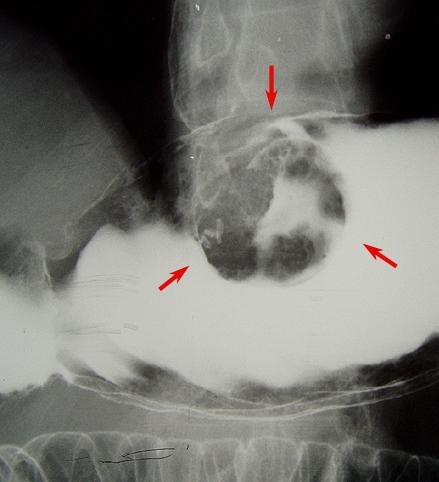

Criteria of Hist.ClassificationMalignant epithelial tumor/Adenocarcinoma

LocationStomach/Gastroesophageal junction

Technique, MethodX-ray

Macroscopic TypesType 2 Ulcerated type with clear margin/

Size30 - 34

Depth of Tumor Invasionsubserosa (subadventitia)